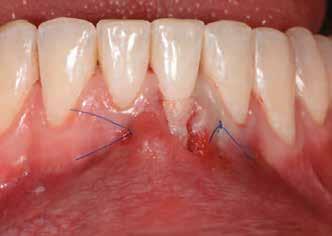

Az eljárást helyi érzéstelenítés mellett végeztük (4%-os articaine-hidroklorid 1:100 000 adrenalinnal). Papillakímélő, U alakú palatális bemetszést végeztünk, teljes vastagságú nyálkahártyalebeny preparálás történt, a lebenyt bukkálisan feltekertük (5. ábra). A lebeny bukkálisan feltekert részén de-epitelizációt végeztük el, amellyel kompenzálni tudtuk a bukkális lágyszöveti defektust. Szakaszos előfúrást végeztünk, és a bredent copaSKY 4x10 implantátumot 30 Ncm behajtási nyomatékkal helyeztük be (6. ábra). Az implantátumot 1 mm-re szubkresztálisan helyeztük be, hogy később szélesebb emergenciaprofilt tudjunk kialakítani (7. ábra). Az egyedi ínyformázó úgy készült, hogy kompozitot vittünk fel a titánbázisra, és így formáztuk a lágyszöveteket a transzgingivális gyógyulási fázis során (8. ábra). Az egyéni ínyformázó tulipán formájú, hogy kialakítsa a kívánt emergenciaprofilt. A lágyszövetet feszülésmentesen zártuk #6/0 nem felszívódó, monofil fonallal (Optilene, B. Braun Deutschland; 9. a–b. ábra). Posztoperatív röntgenfelvétel készült, ami alapján az implantátum a szomszédos fogakkal párhuzamos elhelyezést mutatott (10. ábra). Posztoperatív utasításokat adtunk a páciensnek a műtéti terület körüli szájhigiénia fenntartása érdekében. A beavatkozást követő egy héttel a varratokat eltávolítottuk, és a kezelt terület kielégítő gyógyulást mutatott (11. ábra). A 4 hónap utáni késleltetett terhelést a páciens kívánsága szerint terveztük.

9. b. ábra: Feszülésmentes zárás